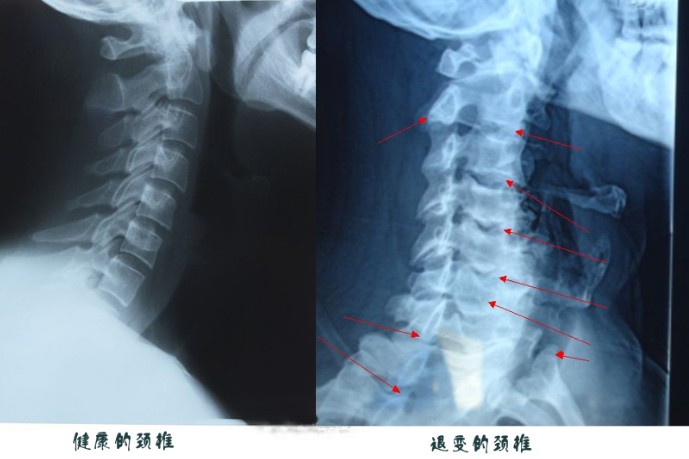

台中中港医院复健科医师杨镇嘉直言,自己也被这名男子的颈椎X光吓到,其第4、5、6节的椎体变形,间隔变窄,还有明显的骨刺,已压迫到神经,看起来就像70多岁老人已经退化的颈椎。这与他经常长时间玩手机的习惯不无关系。

杨镇嘉说,一般脊椎慢性退化病变都出现在颈椎第5、6、7节,低头族则在第4、5、6节。以前患者多是生产线的作业员,现在则大多是手机低头族,各个年龄段都会发生。尤其是经常躺卧在床上玩手机,颈椎弯曲角度更大,症状加速恶化,如不改善,甚至要开刀治疗。